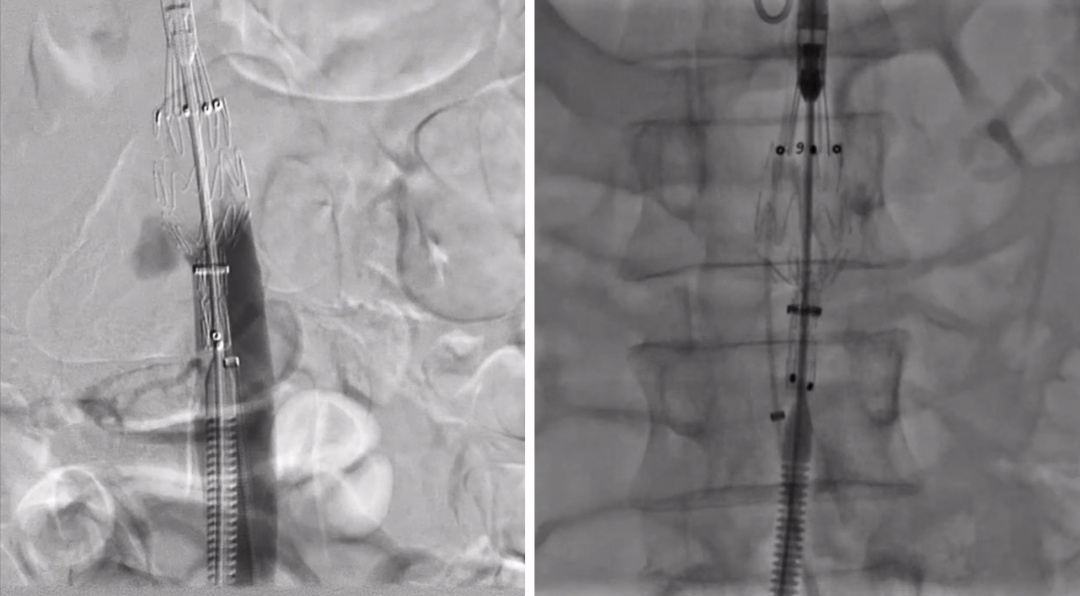

腹主动脉假性动脉瘤(Medtronic cuff 23mm×23mm×45mm)近端平齐左肾动脉下缘,远端保留肠系膜下动脉;

RDC Guiding配合导管Interlock-35 20mm×40cm;Interlock-18 14mm×30cm可控弹簧圈栓塞右肾动脉瘤;

右肾动脉内植入Viabahn 7mm×25mm,超出主动脉内5mm释放